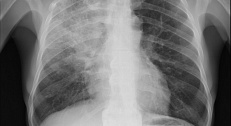

Диагностическая ценность при пневмониях

| Параметр | Вирусные пневмонии (COVID-19, грипп) | Бактериальные пневмонии |

|---|---|---|

| Чувствительность | 89-94% | 76-85% |

| Специфичность | 95-99% | 90-94%

|

- Вирусы чаще вызывают диффузное поражение альвеол → четкая корреляция SpO₂ с PaO₂

- Бактериальные пневмонии могут давать локальные инфильтраты → возможны ложнонормальные показатели